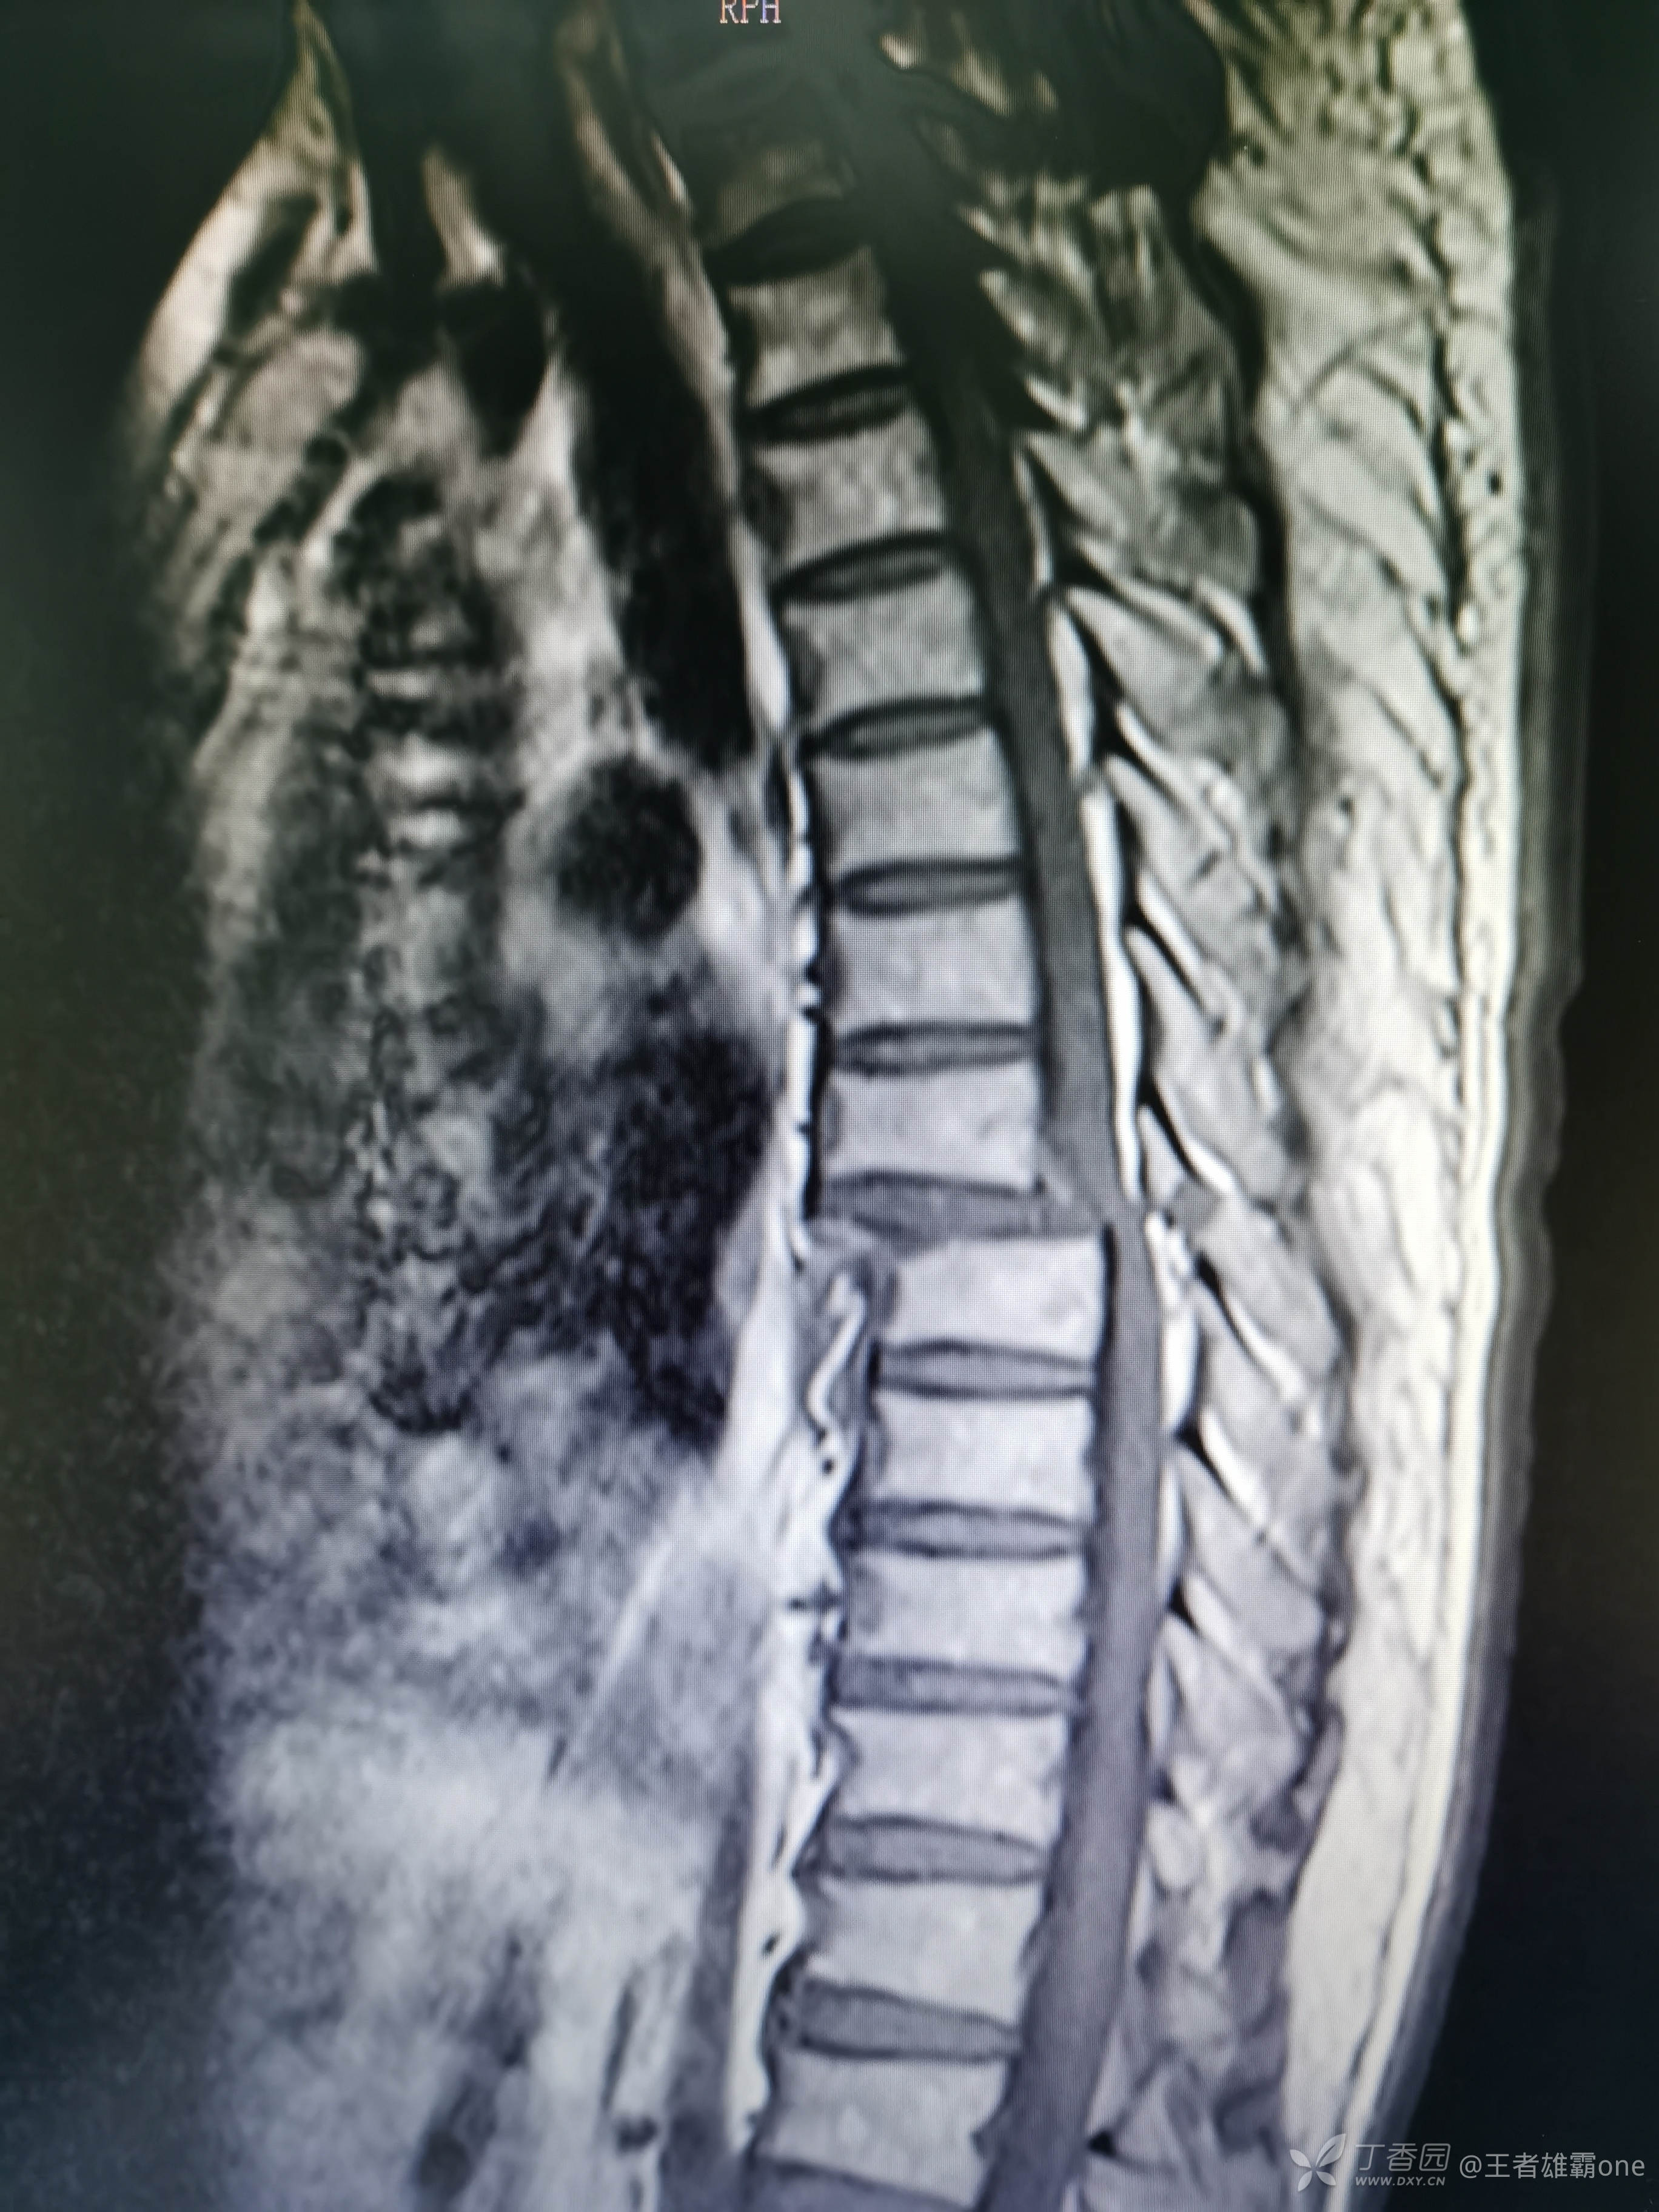

查胸椎MR: